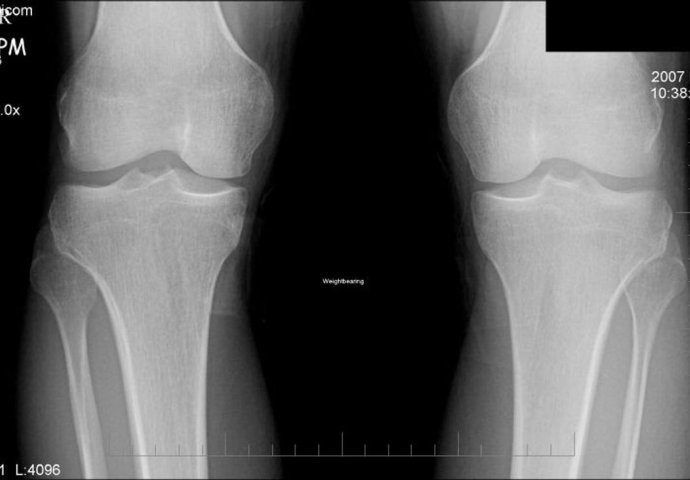

Kod svih oboljenih osoba ne dolazi do pojave svim simptoma, a oboljenje je najlakše otkriti pomoću rendgenskih snimaka.

Dodaje da su simptomi i povremeno oticanje, toplina i otečenost zglobova koljena, gubitak fleksibilnosti, deformacije i kvržice u koljenima, a može dovesti i do invalidnosti. Većina ljudi iznad 60. pokazuje bolest na rendgenskim snimkama, no samo trećina ih ima simptome. No čuju li škripanje u koljenima, u opasnosti su od razvoja kroničnih simptoma, upozoravaju istraživači ove studije provedene na gotovo 3500 sredovječnih i starijih ljudi.